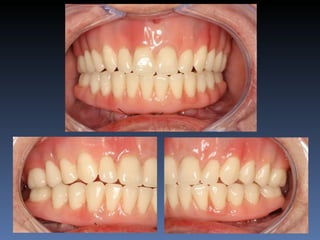

Maurício Zanetti

Idade – 47 anos

Sexo – Masculino

Raça – Caucasiana

ASA – II

Data- 25-04-2012

Diagnóstico: Desdentado parcial

pré-maxila.

Plano de tratamento: Reabilitação pré-maxila com

instalação de 2 implantes endo-ósseos (1.1,.2.2), para

reabilitação protética fixa.